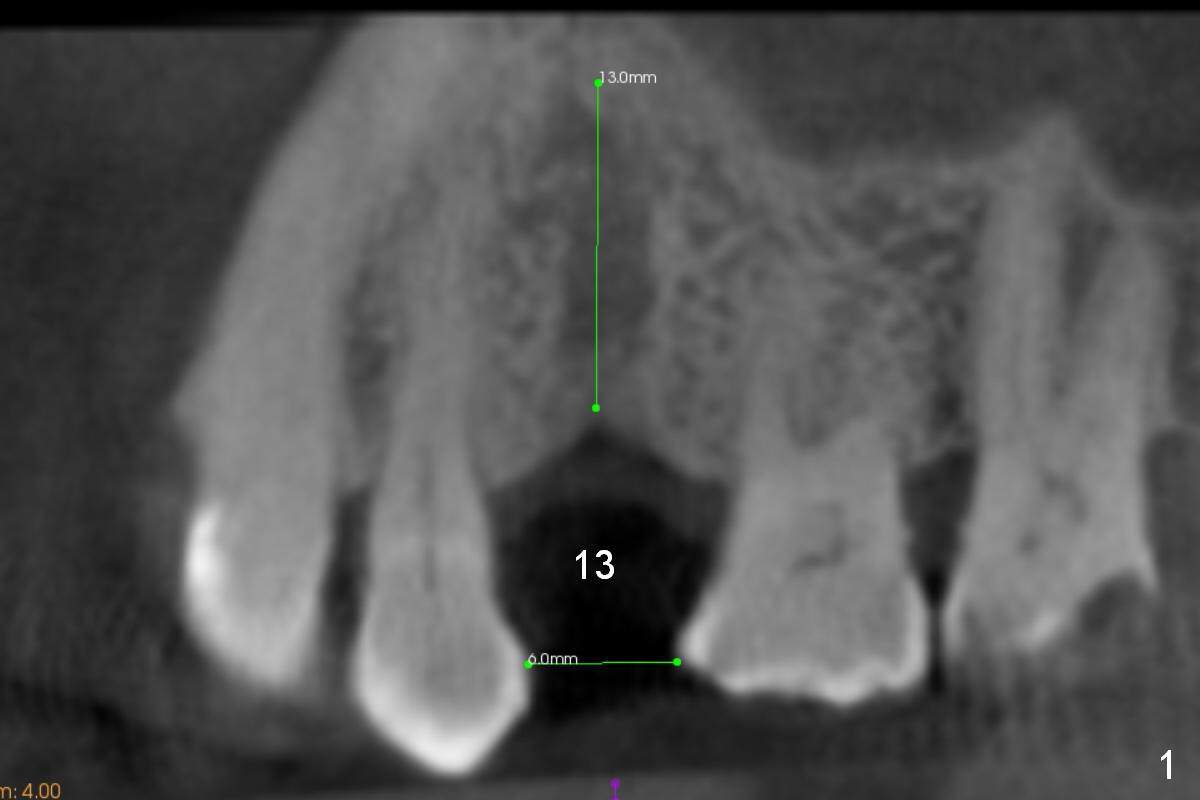

A 74-year-old man has diabetes. Implant osteointegration appears to be slow at #4, while the implant at #28 failed once. He requests implant at #13 (Fig.1). It seems that the bone is wide enough (8 mm, Fig.2 (CT coronal section) (P: palatal)) to hold a 4 mm implant (Fig.3 (axial section)). Since bone density is low at the coronal (100-200 units) and middle (50-100 units) segments (Fig.2), bone condensation will be beneficial. To facilitate wound healing, flapless approach is adopted using 1.6 mm pilot drill (Fig.4), followed by 1.4/2.6 mm bone expander. In fact there is resistance to expansion in the zone 1. Magic expander (3.0 mm) is also tried with difficulty. It appears that bone density is higher than expected. The second portion of Magic Surgical Kit is then used: 3.3 mm Magic Drill for 15 mm (gingival level, followed by Final Drill). A 4x13 mm IBS implant is seated incompletely. The osteotomy is further enlarged by 3.8 mm Magic Drill for 11 mm and deepened with 3 mm drill until 18 mm. Finally the implant is placed at a satisfactory level with insertion torque > 50 Ncm (Fig.5). A 4.5x4(3) mm abutment is placed and periodontal dressing is applied. The patient chooses to return for impression 6 months postop (Fig.6). The abutment changes to a 4x4(4) mm one. The crown is recemented nearly 2 years post cementation, which is related to distal and deep placement of the implant and bruxism (Fig.7).